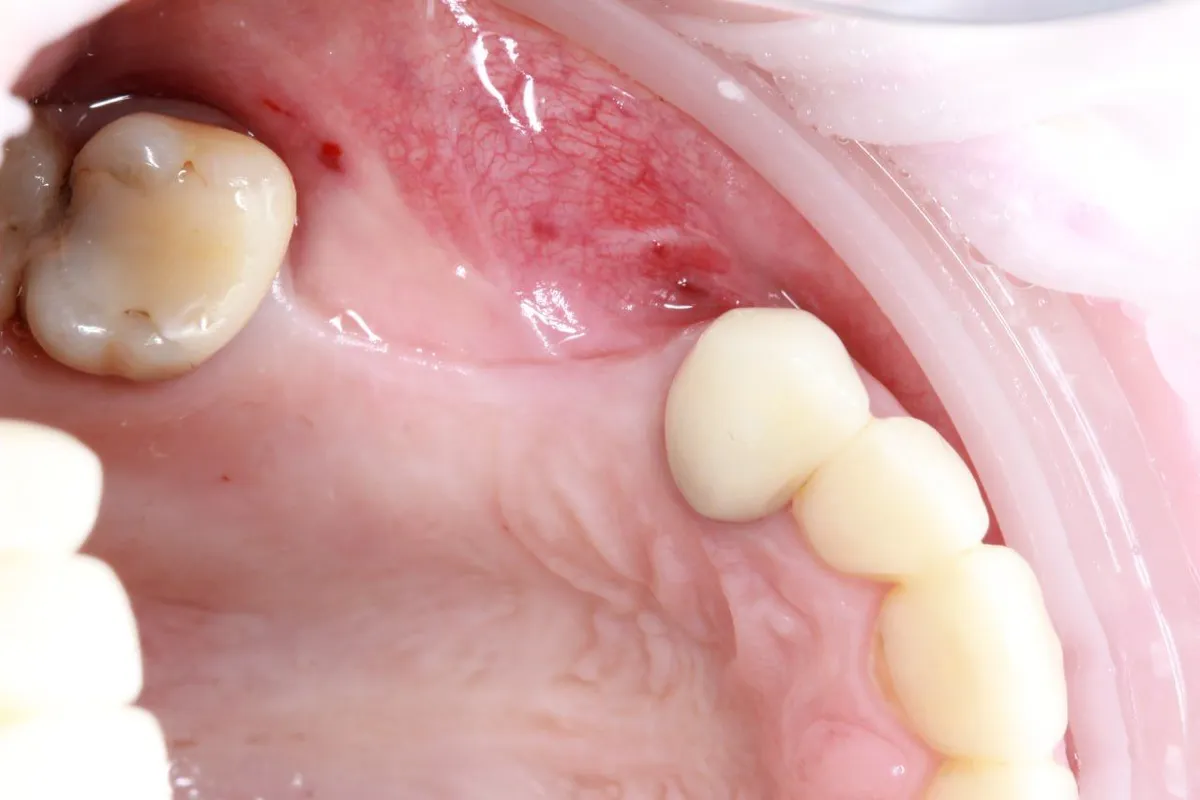

Пациент 42 года, обратился по поводу нарушения эстетики и жевательной эффективности по причине отсуствия зубов на верхней челюсти.

Было принято решение провести установку двух имплантов для дальнейшего протезирование трёх коронок в виде моста с опорой на имплантах на позициях 14 и 16.